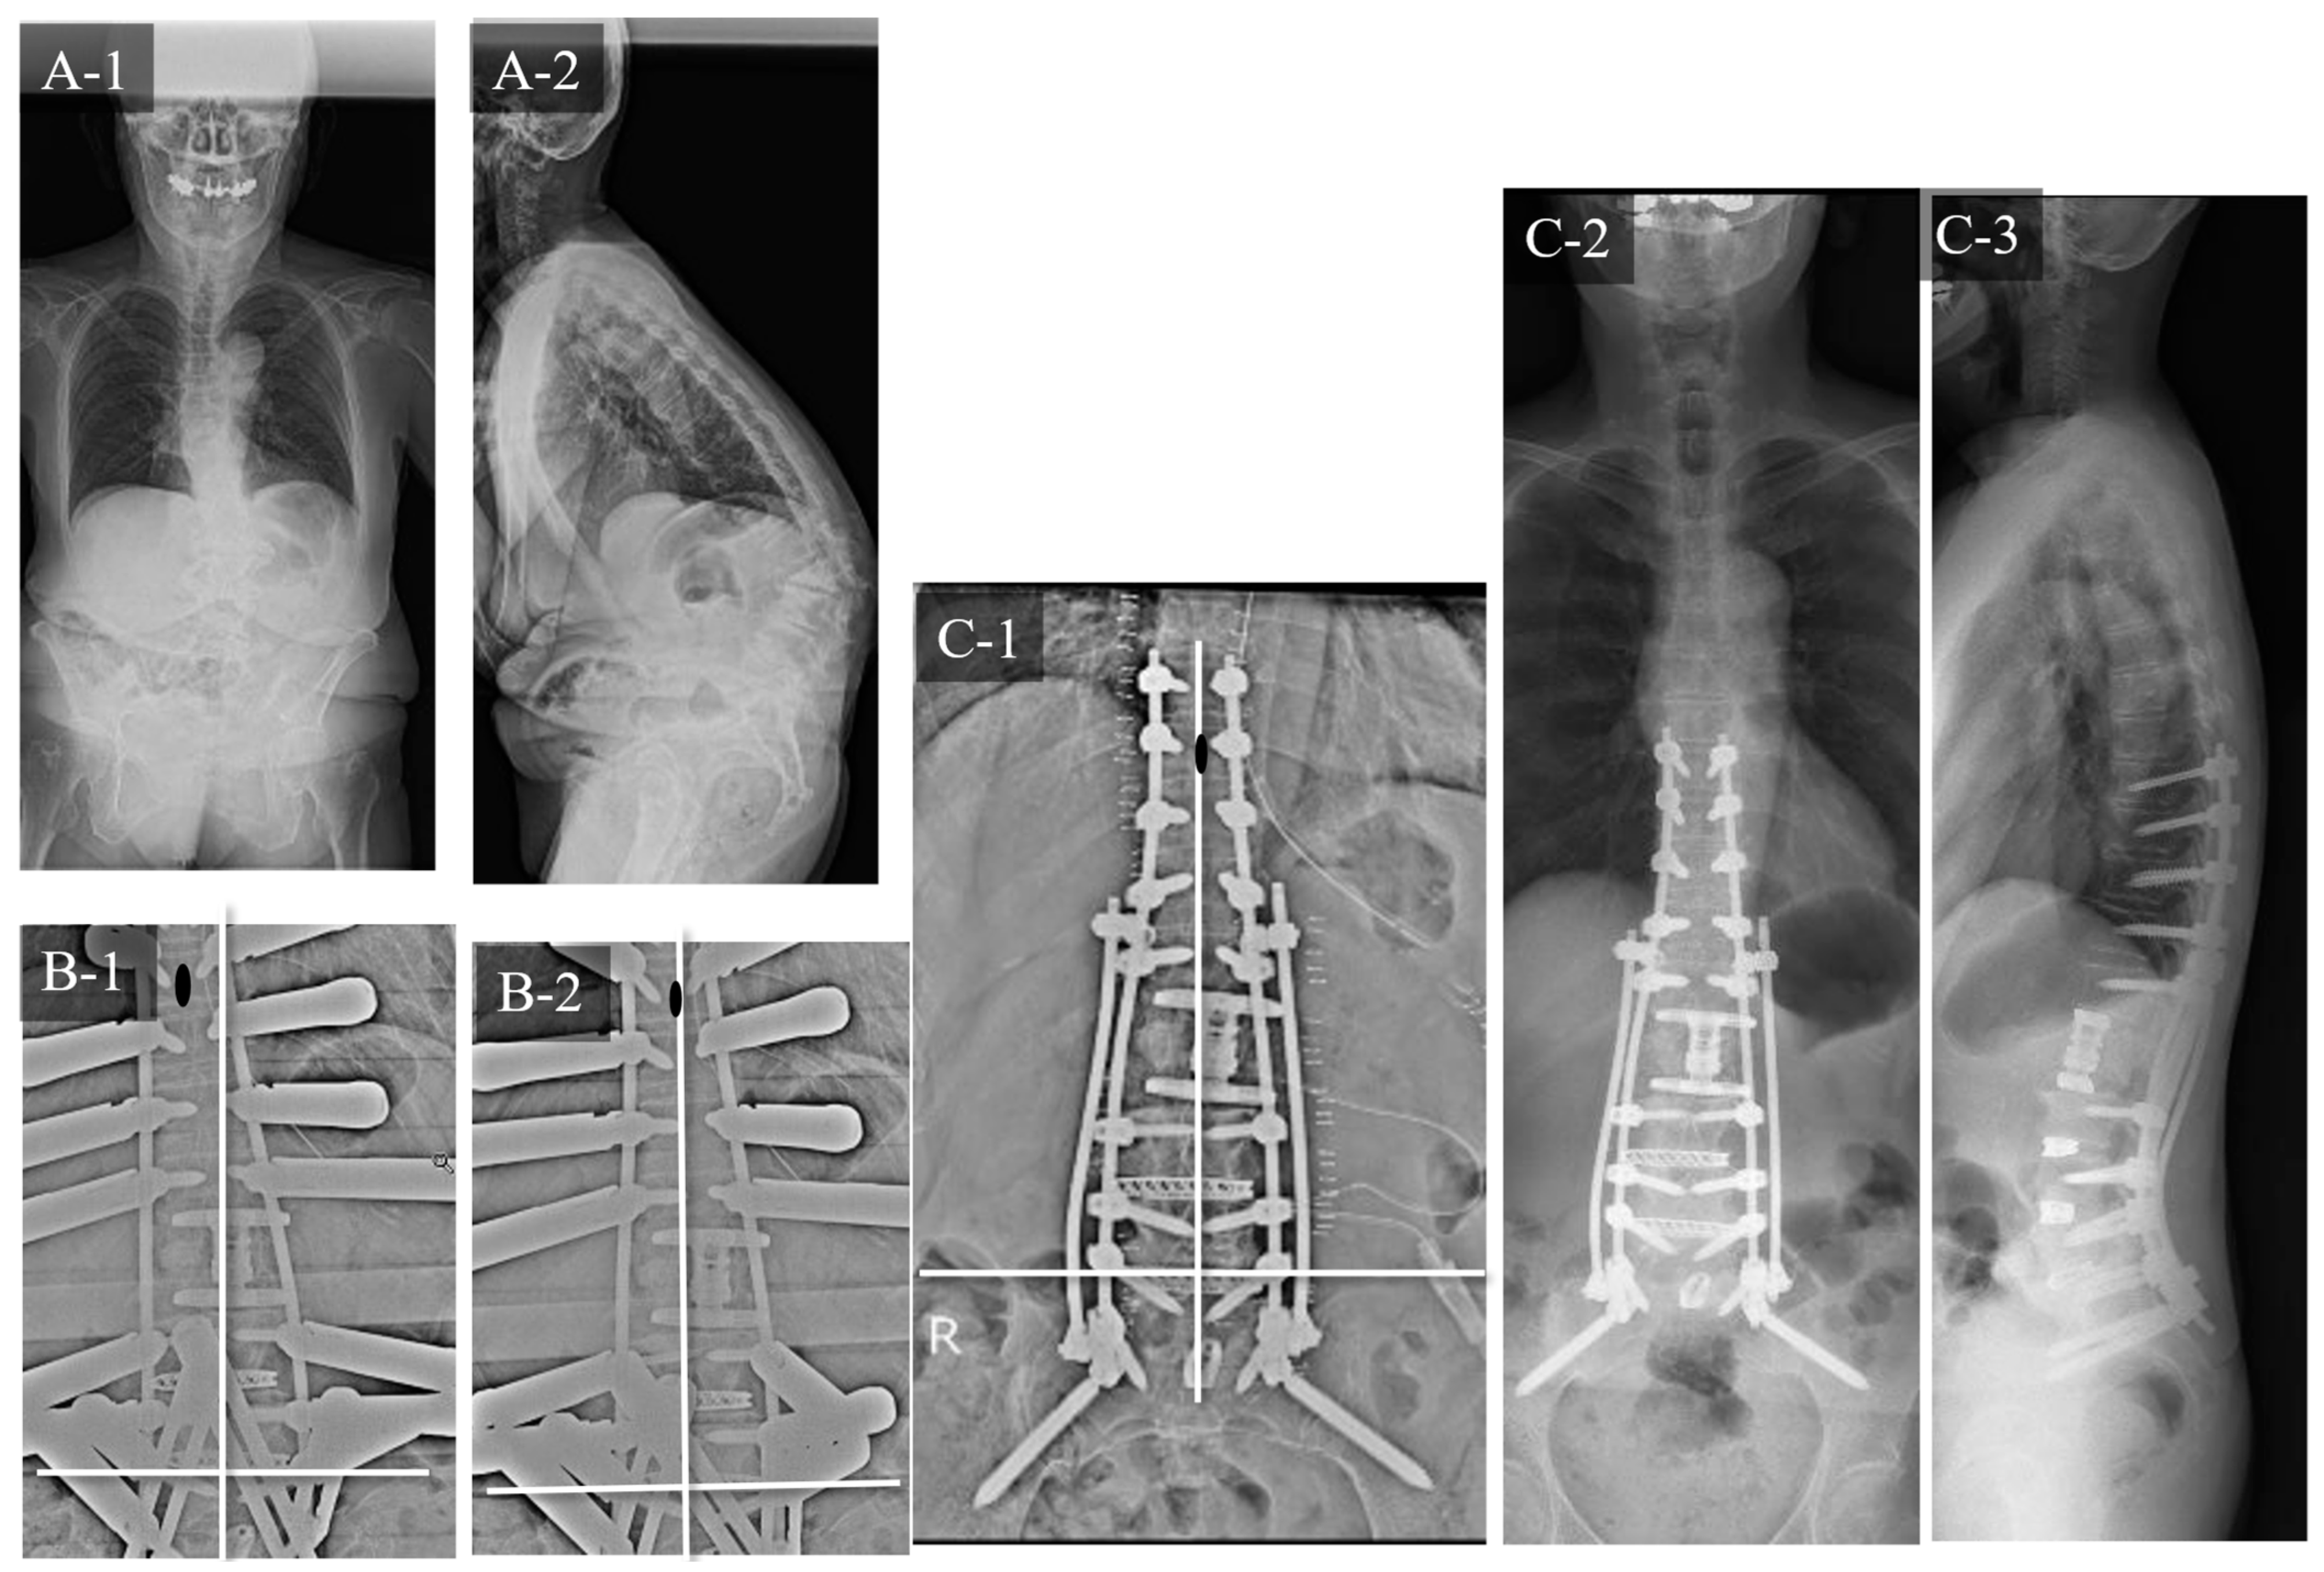

3.2. Case Study 2: RR and SD

3.3. Case Study 3: RR and KR